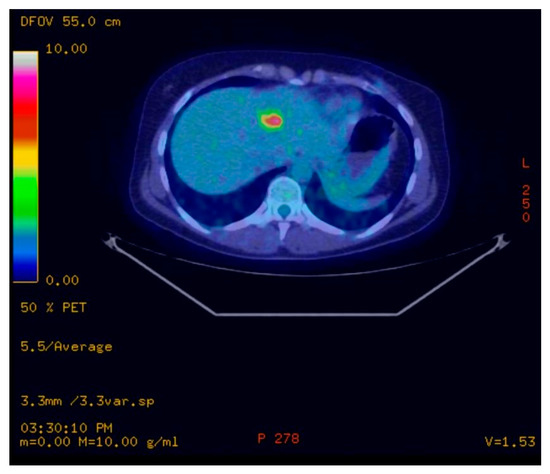

2. Case Presentation